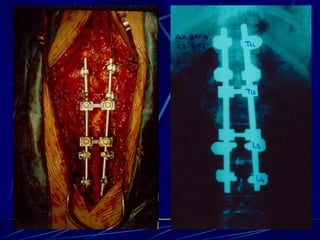

Φυματίωση της σπονδυλικής στήλης